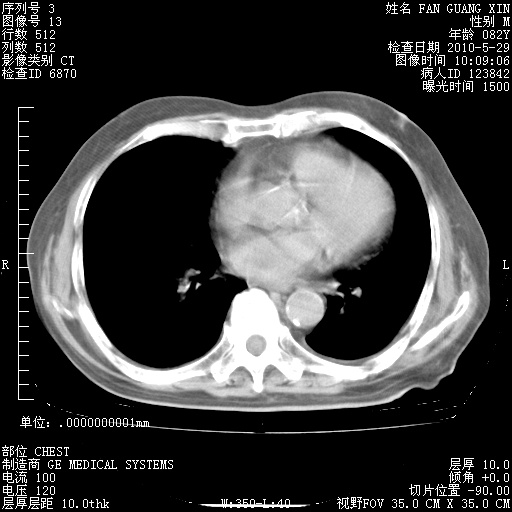

治疗3周后的肺部CT纵隔窗

再治疗10天后的肺部CT 纵膈窗

阅读此次胸部CT,肺间质渗出性改变较入院时有吸收。目前从体温、白细胞、中性分叶明显增高,肯定存在细菌感染(发生医院感染哦,若无消化道及泌尿系统等感染的依据,肺部感染可能大)。若你院头孢哌酮舒巴坦钠耐药率较高,同意你的方案,若48小时体温仍高,可考虑使用碳青霉稀类抗菌药物,同时可予超声雾化、注意滴数时加大液体量。白蛋白33.30g/L较低哦,需加强营养等支持治疗。